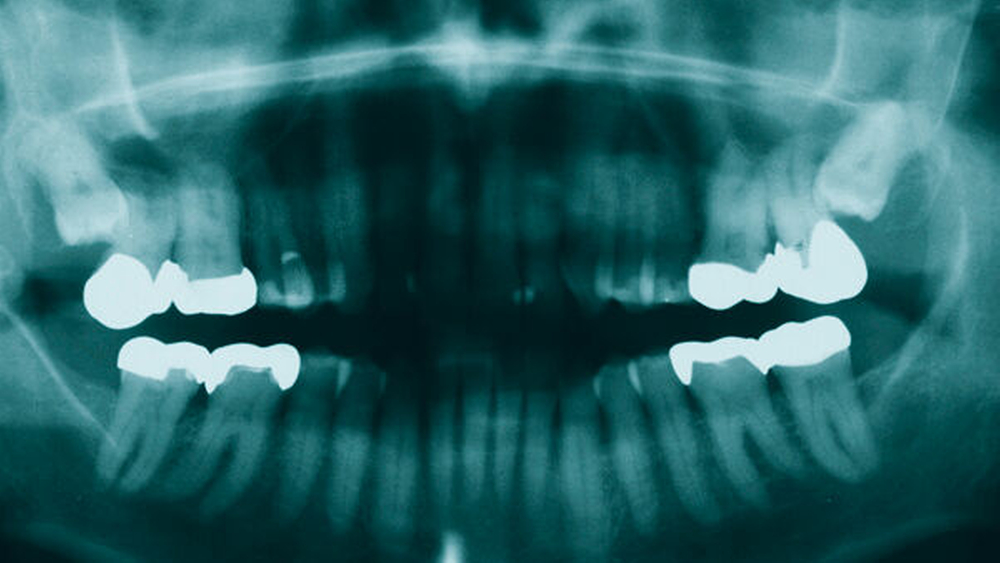

Zur erweiterten radiografischen Diagnostik wurde dann eine dreidimensionale Bildgebung im Sinne einer digitalen Volumentomografie (DVT) des Mittelgesichts angefertigt. Wie in Abbildung 3 zu sehen ist, präsentierte sich im DVT an der medialen Seite im kranialen Drittel des aufsteigenden Astes des Ramus mandibulae am Übergang zum Processus condylaris eine in alle Achsen ausgedehnte, etwa 10 mm x 6 mm große, knochendichte Opazität, deren Form am ehesten mit einer Kidneybohne zu vergleichen war. Diese war, wie in der präoperativen PSA, klar begrenzt, am Rand opak verdichtet und im Zentrum diffus blass opak. Eingelagert war sie in eine lakunenförmige Aussparung des Ramus mandibulae kranio-rostral des Foramen mandibulae ohne erkennbare umliegende Osteolyse oder Infiltration. Ideal erkennbar war die beschriebene Struktur in der markierten Ebene der koronalen Schicht.